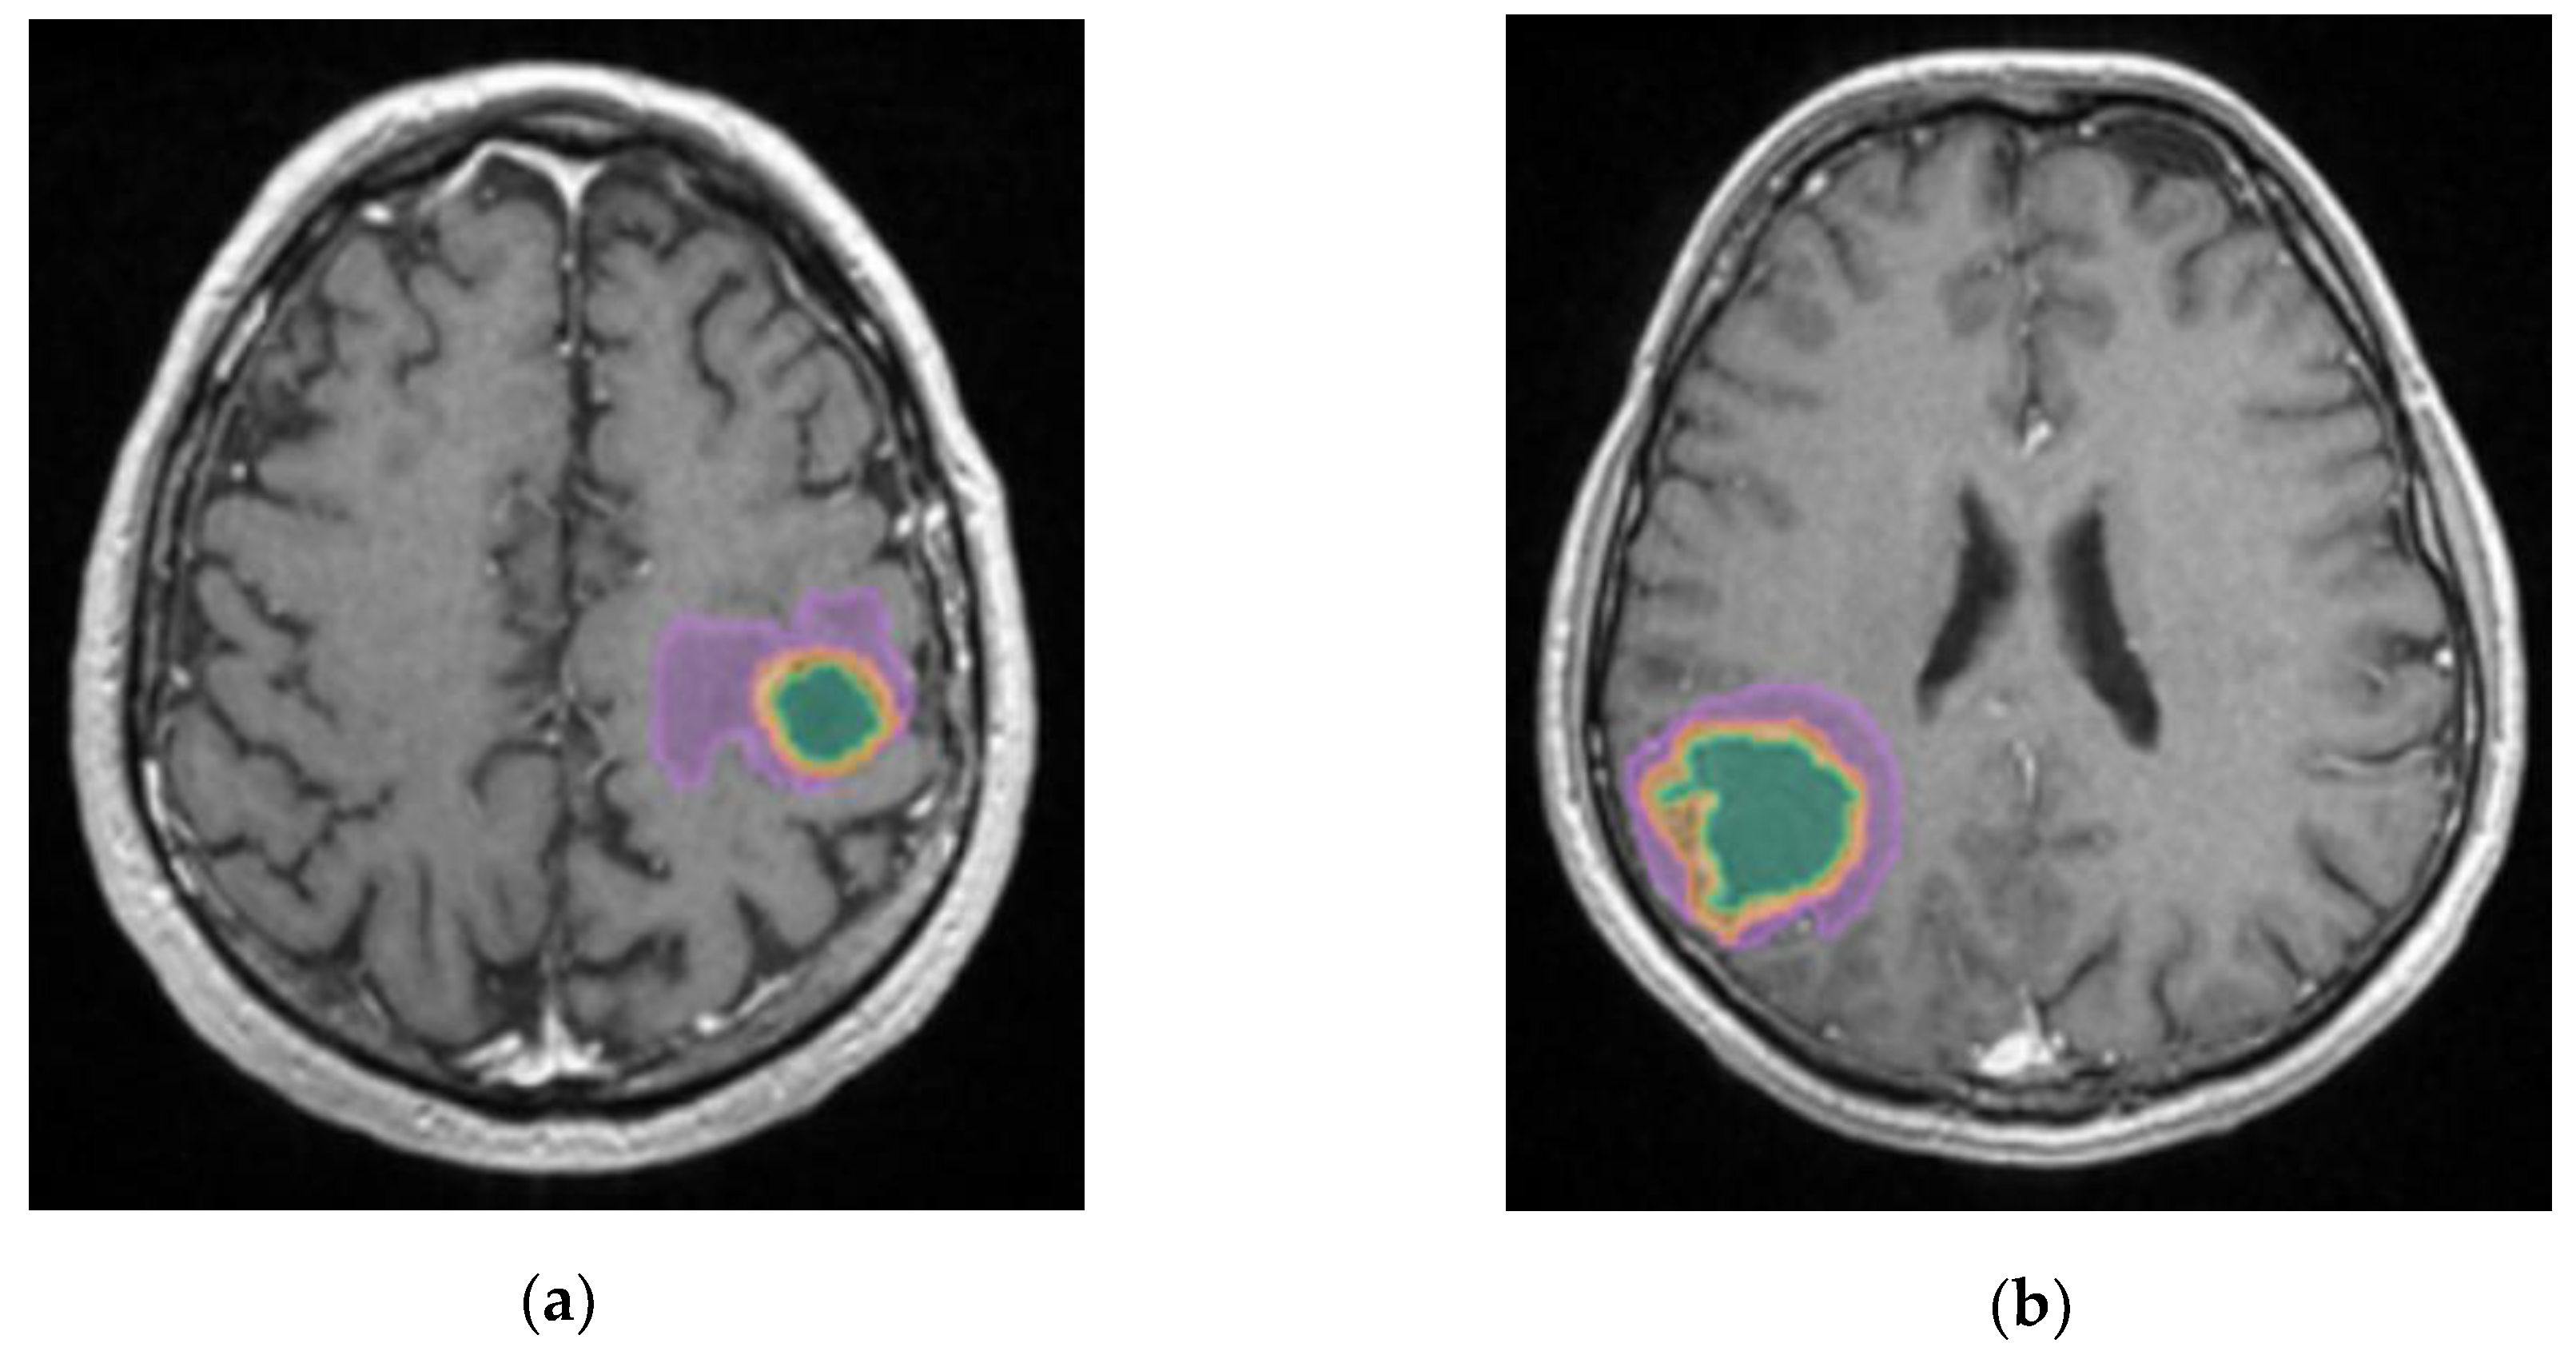

Figure 10.

Mdbrain processing of MRI brain acquisition (DICOM). (a) T1W CE +FLAIR, axial plane, green area corresponding to the cystic portion of the lesion; (b) T1W CE+FLAIR, axial plane, green area corresponding to the necrotic center (approval was obtained from the Ethics Committee of the University of Medicine and Pharmacy “Grigore T. Popa” Iasi).

The most edematous secondary lesions were from lung cancer, especially NSCLC, followed by digestive carcinomas, breast and melanoma, with the least edematous being the BM from renal and colorectal carcinomas (p=0.01). On the other hand, the most necrotic ones derived from colorectal and renal carcinomas (p=0.01); this finding could be the result of scarce identification of cystic lesions by the AI model, as necrotic tissues and cystic transformation of lesions are quite similar on T2W FLAIR images.

A better identification of cystic components and necrotic central tissue could be obtained by analyzing the contour defined by the lesion border, as necrotic borders are irregular and anfractuous, differing in thickness. In contrast, cystic walls are well delineated and smooth, having a more rounded shape (see

Figure 10) [

20].

Consequently, more studies should focus on this aspect, as their following implications are very different. Cystic lesions are radiotherapy resistant, often developing radiation necrosis, and their content is usually evacuated prior to other treatment. On the other hand, necrotic areas are surgically excised along with the tumor [